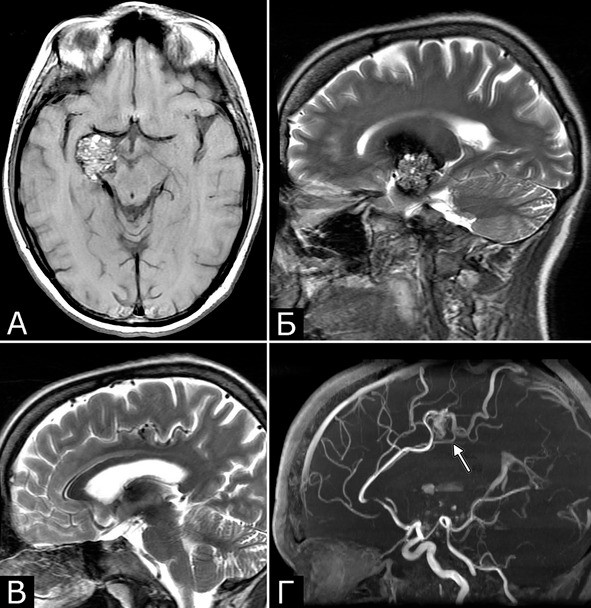

Сочетание каверномы с АВМ выявлено у двух больных, причем в обоих случаях клинические проявления заболевания были обусловлены АВМ, а кавернома явилась случайной находкой (рис. 1).

Рис. 1.Б-ная Г., 27 лет. Сочетанная сосудистая патология мозга: КМ передне-медиальных отделов височной доли справа (А – МРТ, режим Т1; Б – МРТ, режим Т2); АВМ медиальных отделов лобно-теменной области справа (В – МРТ, режим Т2;Г – МРТ-АГ). Клиническое течение: редкие вторично-генерализованные судорожные эпилептические припадки, начинающиеся с судорог в левых конечностях

Рис. 2.Б-ной П, 22 г. Сочетанная сосудистая патология мозга: Множественные КМ головного мозга. Аномалия развития венозной системы мозга. А – КМ височной, теменной и затылочной долей слева (МРТ, режим Т2, аксиальная проекция). Б, В – аномалия развития костей и оболочек мозга в виде локальной деформации внутренней костной пластинки и губчатого вещества теменных костей в области впадения патологической вены в ВСС. Расщепление аномального ВСС на две лакуны, пролабирование мозга в область дефекта (МРТ, режим Т1, сагиттальная и фронтальная проекции). Г – аномалия венозной системы в виде отсутствия прямого синуса, формирования крупной патологической вены, впадающей в заднюю треть ВСС (МРТ-АГ, сагиттальная проекция)